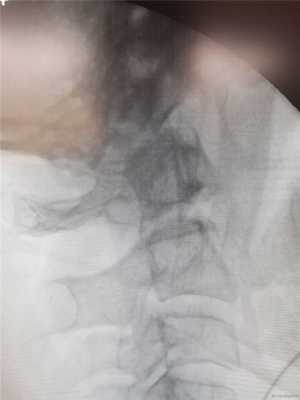

Автотравма. Удар лбом о переднее сидение. Доставлена в реанимацию с глубоким тетрапарезом. На фоне лечения сила в ногах наросла, руки по-прежнему слабые.

На операции в скобе Мейфилда репозиция вывиха С1.